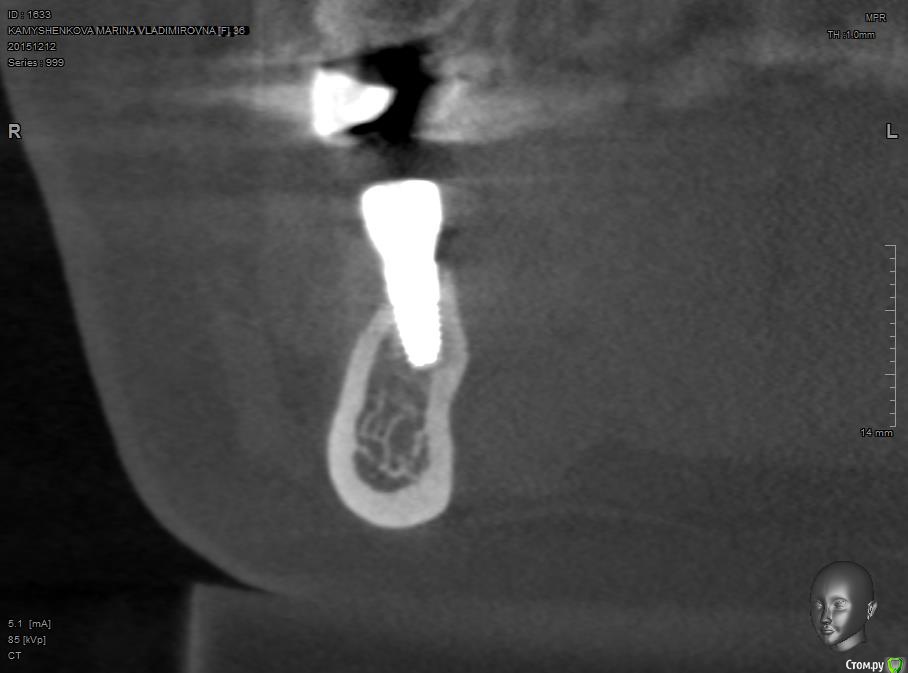

Павел7809 Опубликовано 19 января, 2016 Поделиться Опубликовано 19 января, 2016 Чтобы не плодить темы закину фотку сюда. Ситуация нелепая....При установке намертво заклинило наконечник, и не было возможности доработать ложе....недокрутил порядка 1.5 мм из 8 (с бешеным торком, по ощущениям около 70). Кт сделано уже после интеграции... Ссылка на комментарий

k.t.m. Опубликовано 19 января, 2016 Поделиться Опубликовано 19 января, 2016 Чтобы не плодить темы закину фотку сюда. Ситуация нелепая....При установке намертво заклинило наконечник, и не было возможности доработать ложе....недокрутил порядка 1.5 мм из 8 (с бешеным торком, по ощущениям около 70). Кт сделано уже после интеграции... а что тут оценивать,надо исправлять или шаманить с мягкими тканями и надеятся. У ортопеда нет права на ошибку, прилегание должно быть идеальное'и гигиена у пациента тоже. Перед имплантацией кт не было? Почему направление такое? И возможно вам кортикалка язычная так и не дала бы возможность заглубить если наконечник был исправлен. Ссылка на комментарий

Павел7809 Опубликовано 20 января, 2016 Поделиться Опубликовано 20 января, 2016 а что тут оценивать,надо исправлять или шаманить с мягкими тканями и надеятся. У ортопеда нет права на ошибку, прилегание должно быть идеальное'и гигиена у пациента тоже. Перед имплантацией кт не было? Почему направление такое? И возможно вам кортикалка язычная так и не дала бы возможность заглубить если наконечник был исправлен.Кт было. Убыли кости небыло вообще. Направление спланировано именно такое и полностью соответствует оси зуба. Ссылка на комментарий